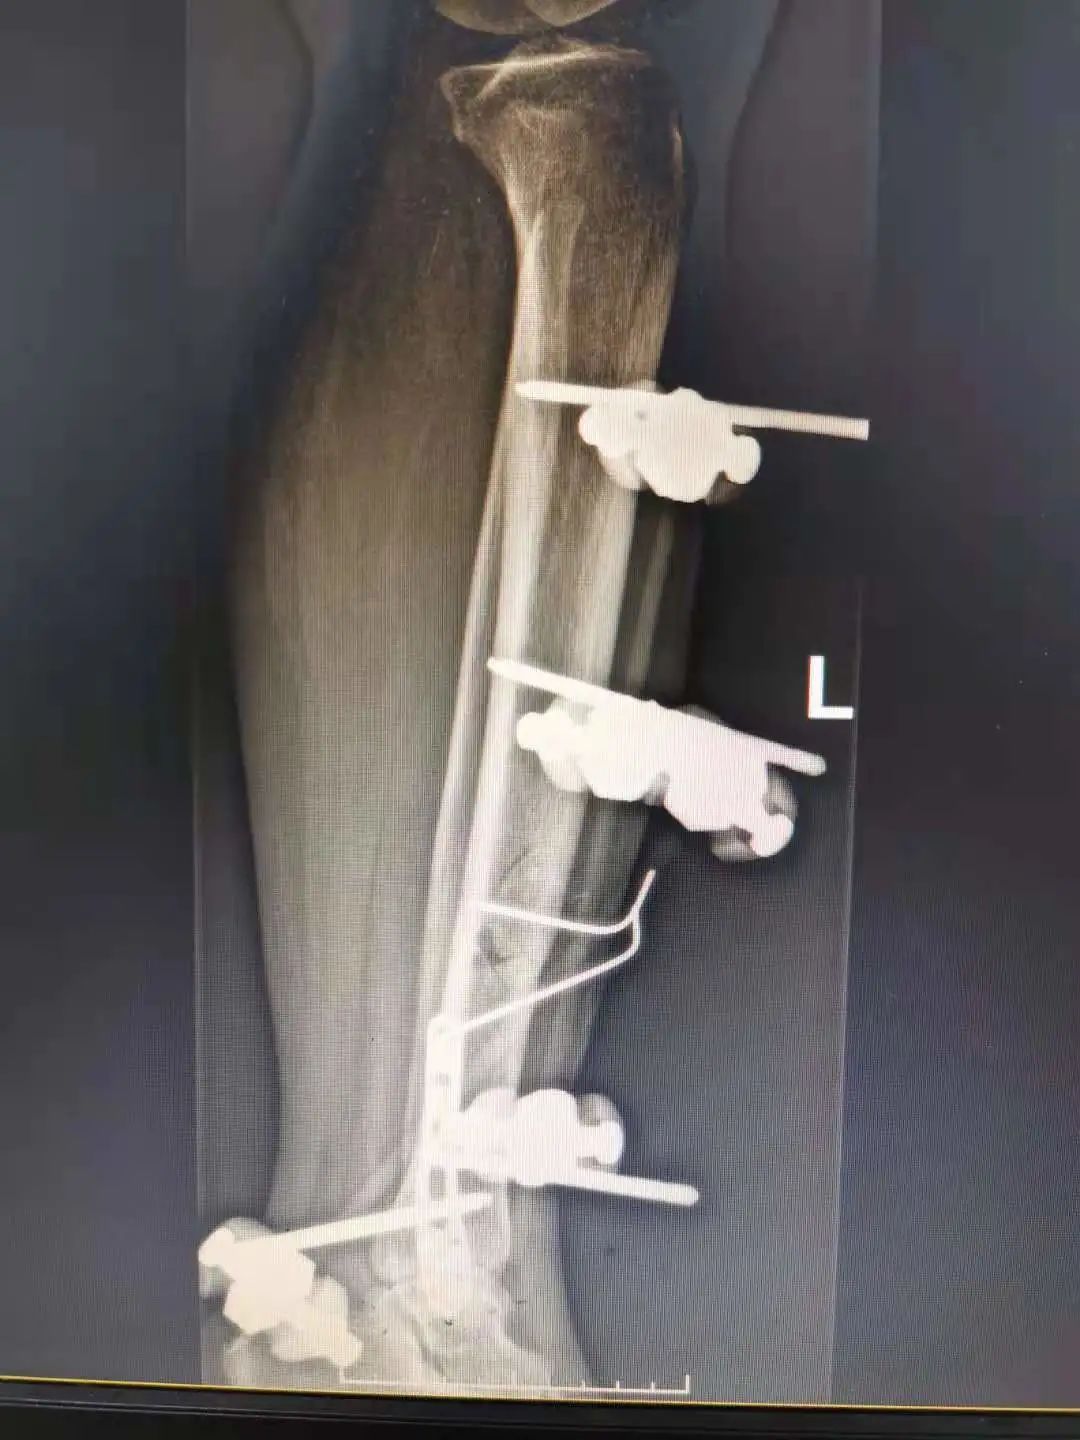

针对吕女士的伤情,骨科一区团队在副主任徐爱贤的带领下进行了周密讨论,对吕女士骨折的治疗方案有两种:一种是内固定,就是将断裂的胫骨复位后用钢板固定;一种是外固定,就是通过一种固定骨骼的器具,在病人骨骼上打入数枚钢针,再安装特制的支架进行固定。选择哪一种方案最

有利于患者呢?胫骨由于其生理特点,骨折好发于中下段,血运差,前内侧软组织覆盖少,如果选择内固定特别是钢板固定,需要剥离骨膜及周围组织,影响断端血运,而且吕女士为开放性骨折,更易发生感染。外固定架可明显避免上述不良影响,更加适合吕女士,且微创,更有利于患者恢

复。

经过与患者及家属的详细沟通,最终确定了外固定的手术方案。经过精心的准备,手术由副主任王学磊主刀,采用“清创+修复软组织+外固定架固定骨折+左侧腓骨骨折切开复位内固定”的方式,用了将近1个半小时,清创彻底、微创固定,手术顺利完成,几天后吕女士顺利拆线出院。